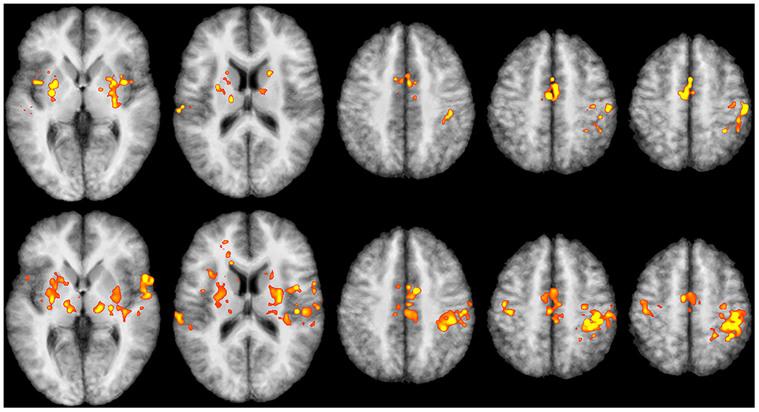

Real-time functional Magnetic Resonance Imaging (rtfMRI) is used mainly for neurofeedback or for brain-computer interfaces (BCI). But multi-site rtfMRI could in fact help in the application of new interactive paradigms such as the monitoring of mutual information flow or the controlling of objects in shared virtual environments. For that reason, a previously developed framework that provided an integrated control and data analysis of rtfMRI experiments was extended to enable multi-site rtfMRI. Important new components included a data exchange platform for analyzing the data of both MR scanners independently and/or jointly. Information related to brain activation can be displayed separately or in a shared view. However, a signal calibration procedure had to be developed and integrated in order to permit the connecting of sites that had different hardware and to account for different inter-individual brain activation levels. The framework was successfully validated in a proof-of-principle study with twelve volunteers. Thus the overall concept, the calibration of grossly differing signals, and BCI functionality on each site proved to work as required. To model interactions between brains in real-time, more complex rules utilizing mutual activation patterns could easily be implemented to allow for new kinds of social fMRI experiments.

实时功能磁共振成像(rtfMRI)主要用于神经反馈或脑机接口(BCI)。但事实上,多站点rtfMRI有助于新交互范式的应用,如监测互信息流或在共享虚拟环境中控制对象。因此,一个先前开发的用于rtfMRI实验综合控制和数据分析的框架被扩展以支持多站点rtfMRI。重要的新组件包括一个数据交换平台,用于独立和/或联合分析两台磁共振扫描仪的数据。与大脑激活相关的信息可以单独显示或在共享视图中显示。然而,必须开发并集成一个信号校准程序,以允许连接具有不同硬件的站点,并考虑个体间不同的大脑激活水平。该框架在一项有12名志愿者参与的原理验证研究中得到成功验证。因此,整体概念、对差异极大的信号进行校准以及每个站点的BCI功能均按要求运行。为了实时模拟大脑之间的交互,可以轻松实施利用相互激活模式的更复杂规则,以开展新型社会功能磁共振成像实验。